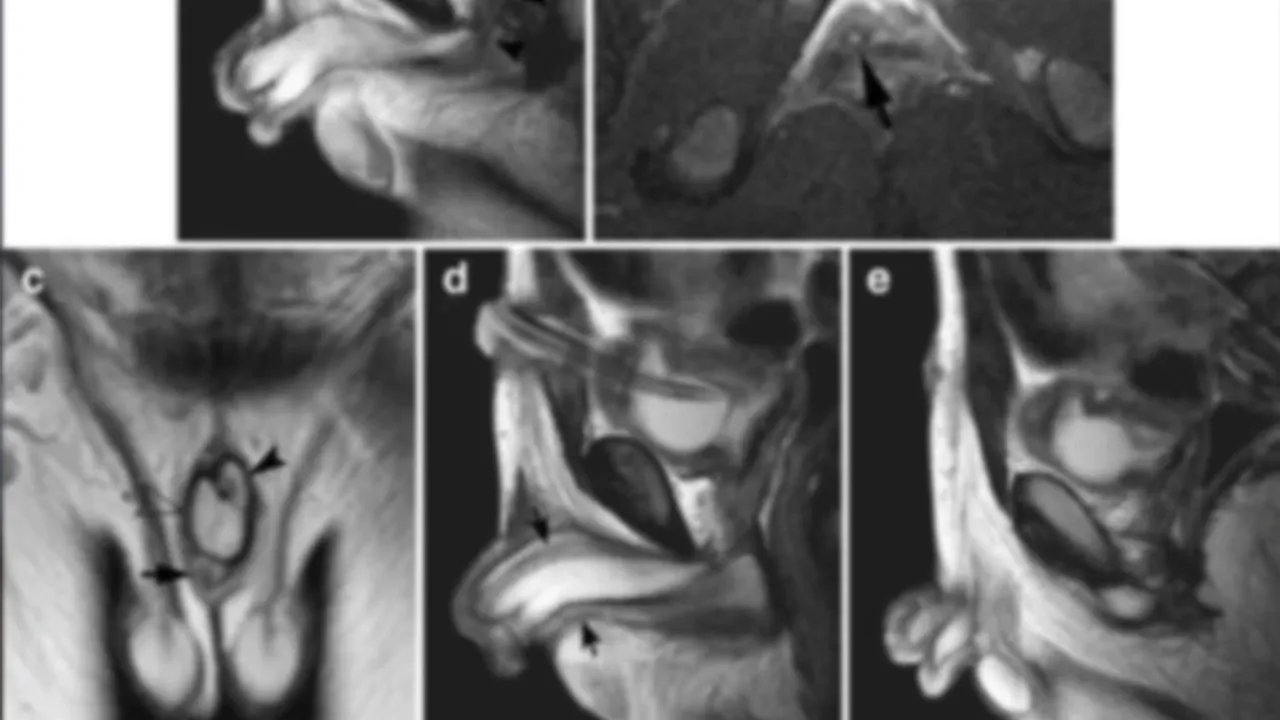

Hastanın kadavrası incelenirken, tıp öğrencileri şok edici bir keşif yaptı. Hastanın ana penisin arka ve alt tarafında, testis torbasının içinde gizlenmiş iki küçük ek penis bulundu. Bu küçük penislerin her biri, kendi sertleşme odacıklarına ve baş kısmına sahipti, ancak ana penisle aynı idrar yolunu paylaşıyorlardı. En küçük penis ise herhangi bir idrar yolu yapısına sahip değildi.